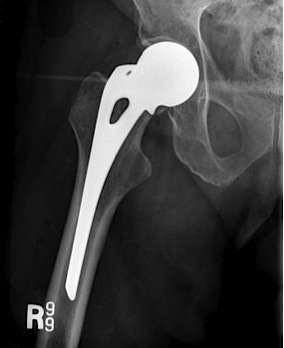

Total hip arthroplasty

Indications

Young, active, mobile patient with neck of femur fracture

Issues

THA

- better functional outcome in young mobile patient

- higher cost

- higher dislocation rates